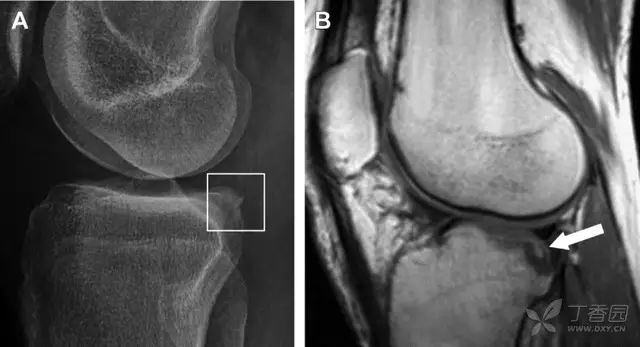

图 2 扭伤后的股骨外侧髁凹陷征

A 侧位片示股骨外侧髁凹陷。B MRI 矢状位 T2 加权像示股骨外侧髁及胫骨后外侧骨挫伤(空箭头)。胫骨近端随着后交叉韧带撕裂发生移位,露出外侧半月板的后角(弧形箭头)。